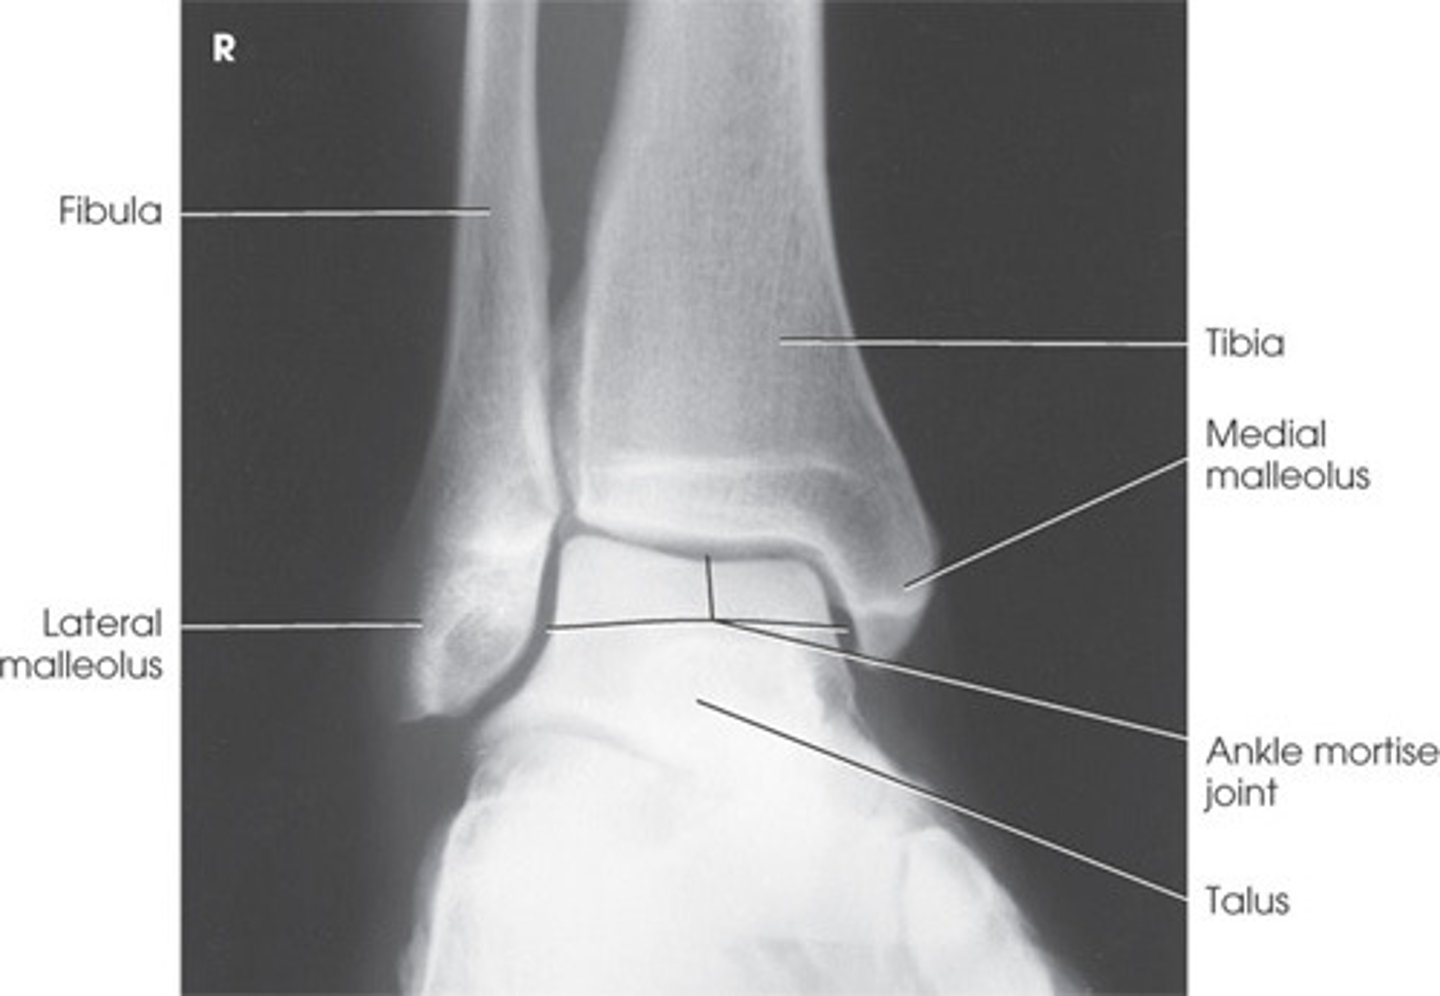

Bones that comprise the ankle (3)

Tibia

Fibula

Talus

Joints of the ankle (3)

Talocrural joint (primary)

In the talocrural joint, is the talus the convex or concave component?

Talus is CONVEX in the talocrural joint

What is the concave component of the talocrural joint?

The tibia and fibula

What type of joint is the talocrural joint? (specific classification based on shape)

Mortise joint